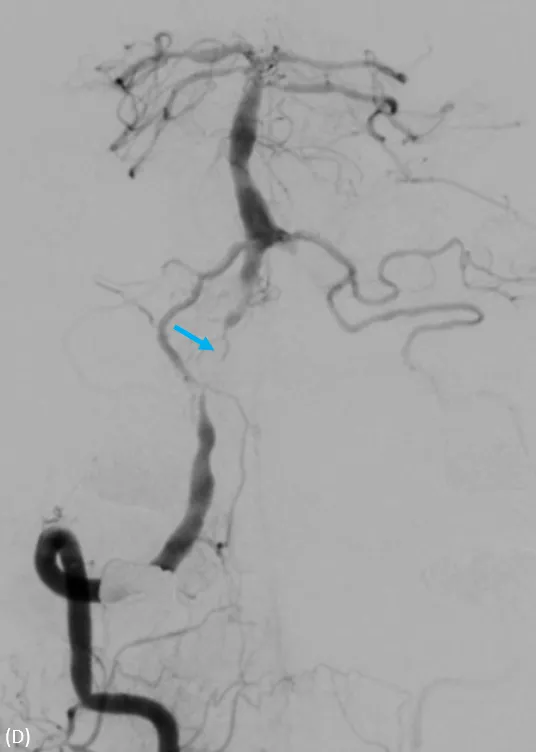

動脈穿刺血管攝影,兩側椎動脈完全阻塞,經由細小分枝供應腦幹的血流。大里仁愛醫院提供